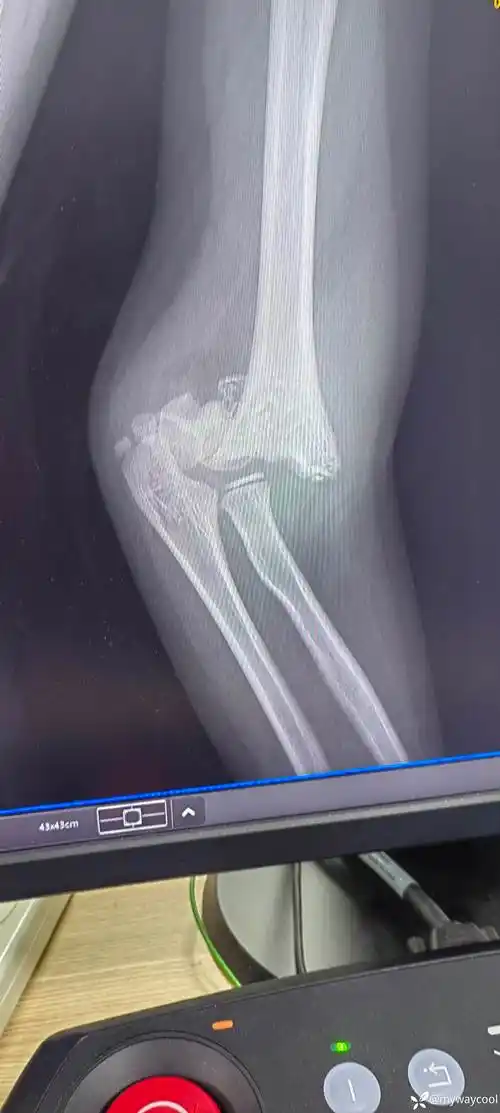

新年第一例肱骨髁上骨折